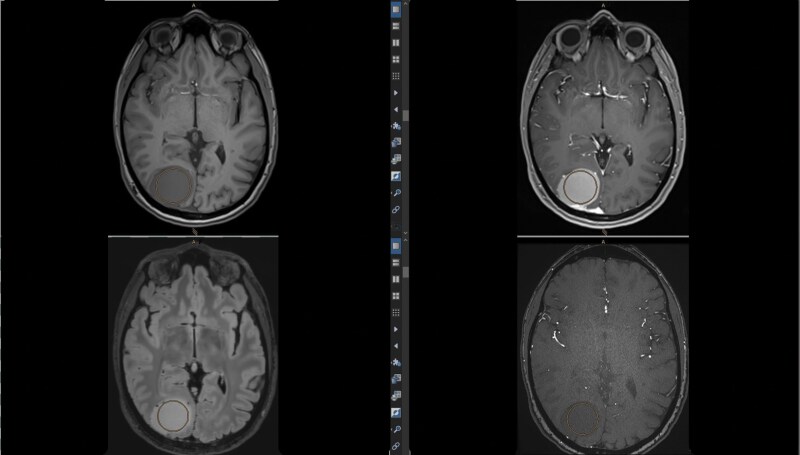

Background: This study aimed to identify magnetic resonance imaging (MRI) markers predictive of essential surgical characteristics in meningiomas, including consistency, ease of dissection of meningioma from surrounding brain tissue, and vascularity, which are crucial for surgical decisions and outcomes.

Methods: We conducted preoperative MRI using a standardized protocol to measure signal intensities (SI) within meningiomas. Additionally, we administered intraoperative questionnaires and performed histological analyses on each tumor.

Results: A total of 100 consecutive patients (mean age, 58 years ± 13, 69 female) were enrolled in this prospective clinical trial. Meningioma volumes varied (0.4-185.6 cm3) with surgeries lasting on average 176 min (range 35-610 min). SI measurements on T1-weighted, time-of-flight (TOF), and T2-weighted imaging were significantly associated with tumor consistency and vascularity. Specifically, the sensitivity and specificity for predicting consistency grades above 3 (on a 1-5 grade scale) were 75% and 55% postcontrast on T1-weighted imaging (SI ≥ 711) and 73% and 70% on TOF imaging (SI ≥ 124.5). For vascularity grades above 5 (on a 1-10 grade scale), the values were 73% sensitivity and 54% specificity on TOF imaging (SI ≥ 123). No correlation was found between the surgical cleavage plane and MRI data; however, dissection plane type significantly influenced surgery duration and hospitalization length. A lower SI on T2-weighted imaging correlated with specific histological features.

Conclusion: Key surgical aspects of meningiomas can be predicted using conventional MRI sequences. This may improve patient counseling and surgical planning.